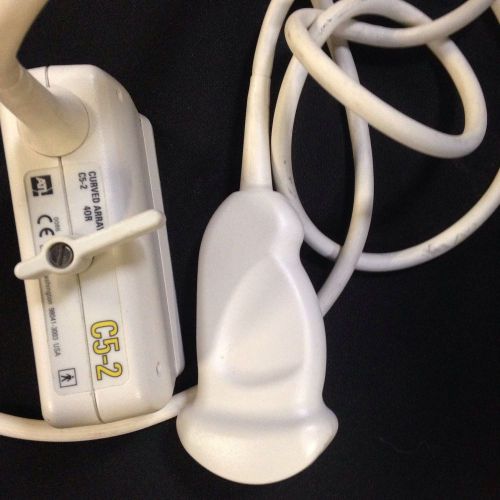

PHILIPS / ATL C5-2 40R ERGO CURVED ARRAY ABDOMINAL ULTRASOUND TRANSDUCER